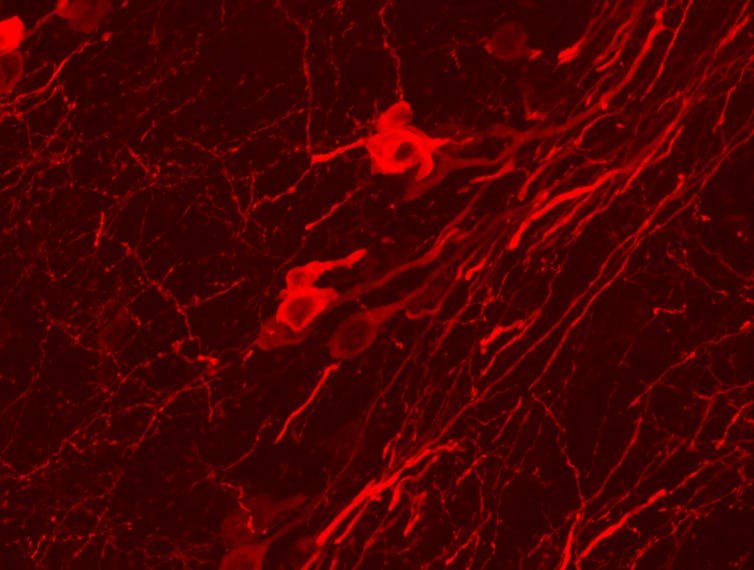

Otra clave es disfrutar de la espera. ¿Por qué estamos ya contentos esperando las vacaciones? Mencionamos unos párrafos atrás la dopamina, que se produce en las neuronas de un par de regiones del cerebro conocidas como Sustancia Negra (por su color oscuro al microscopio) y Área Tegmental Ventral (situadas en el centro de nuestro cerebro, más o menos detrás de las orejas).

Ambas regiones, que en humanos contienen entre 400 000 y 600 000 neuronas, envían axones a numerosas zonas del cerebro. Y a través de la liberación de dopamina juegan un papel clave en la sensación placentera que se genera ante novedades y recompensas. Por eso, saber que vienen las vacaciones aumenta los niveles de dopamina en nuestro cerebro y nos aporta esa sensación de placer.

Lo peor es que los cambios no ocurren únicamente en la Sustancia Negra o en el Área Tegmental Ventral, sino también en los sitios a donde estas mandan sus axones. Se ha visto que el estrés crónico es capaz incluso de cambiar el número de receptores de dopamina en las áreas que reciben sus proyecciones. Cuando esto ocurre, se suelen desarrollar comportamientos depresivos. Por lo tanto, unas vacaciones que nos liberen del estrés ayudarán a reequilibrar el sistema dopaminérgico.